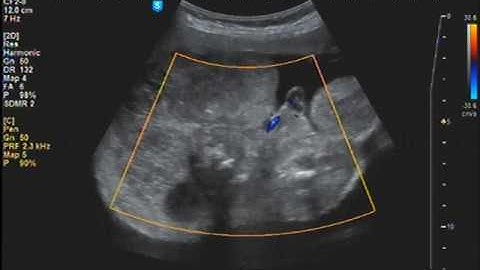

Twin reversed arterial perfusion (TRAP) sequence